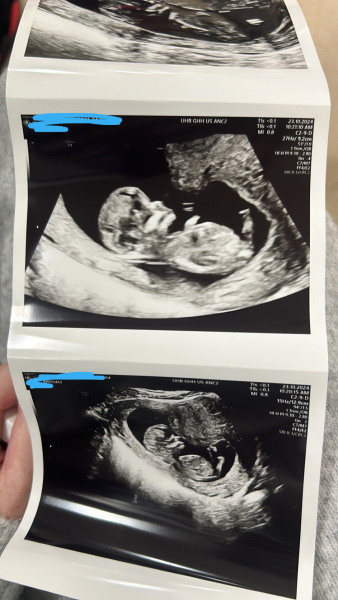

12 weeks 2 days🥹

May 2025 Babies

GraySweatpants · 23/10/2024 13:26

@ThatGladSwan Congrats! Looking very cute and healthy.

Here is mine. Anyone can guess boy or girl cuz I can’t 😆